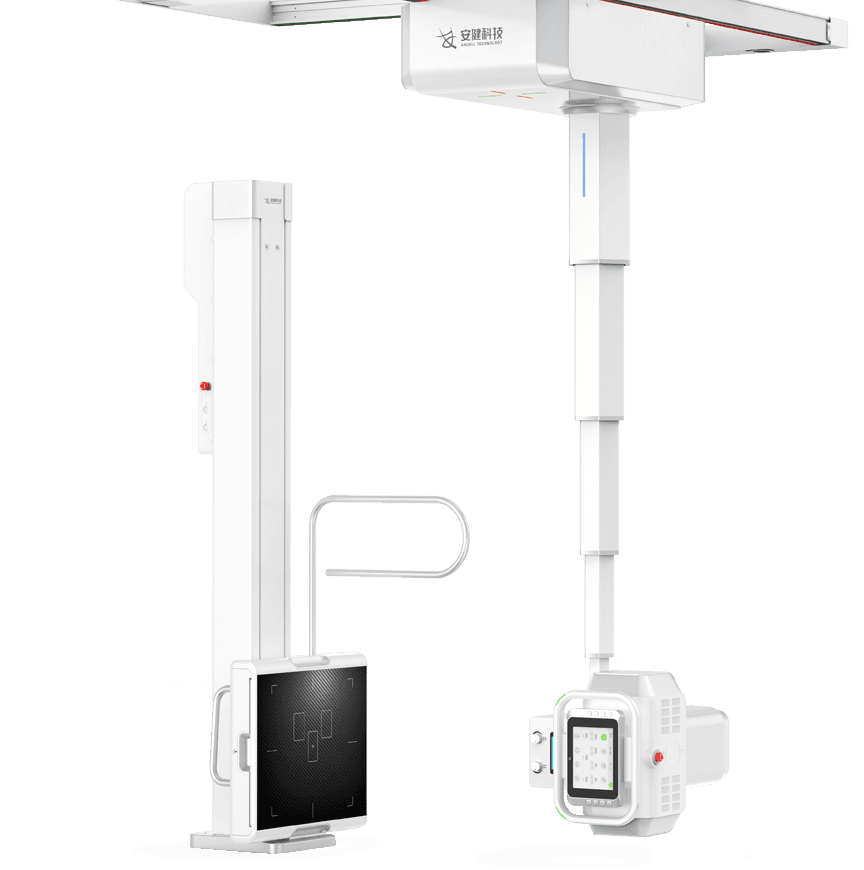

4D十轴联动运动系统

多功能悬吊式机械运动,全平衡稳定性设计,4D十轴联动技术,机架运动自如平稳,

配合电动升降床及多功能立式摄影架,轻松满足临床全体位摄影需求。

球管五向手自一体运动

采用手动与电动一体化设计,并具备感应驱动功能,

一键解锁即可轻松操控球管的全向运动。 -

探测器、球管双向自动跟踪

探测器与球管可实现双向自动跟踪,

立卧位高精度实时同步,大幅提高临床检查效率。 -

全自动长骨拼接

一键式拼接摄影拍摄程序,快速进行分段摄影,后台

自动处理拼接影像,使拼接成像高效精准。 -

立卧位一键切换、—键到位

全自动智能运动控制,射频信号双向接收设计,

实现立卧位一键切换、一键到位,简化操作,提升效率。 -